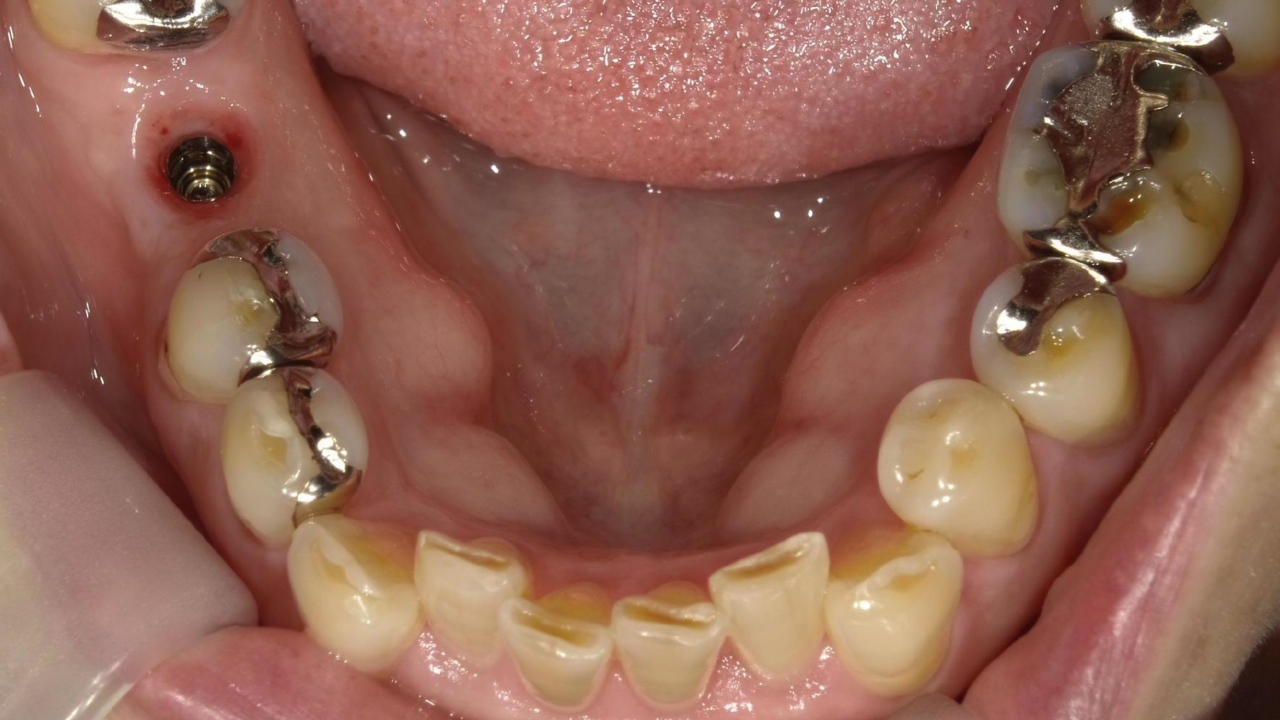

N・H様 女性 70代

Before

After

右下奥歯が噛むと痛くなり、来院されました。レントゲンで歯の根が破折しており、抜歯となりました。抜歯後にインプラント治療を希望され治療を開始。治療後、違和感もなく奥歯で何でも食べれるようになったと満足されていました。

治療期間・回数:11か月、18回

治療の価格:インプラント治療  550,000円 (上部構造含む)

治療のリスクや副作用:手術後に、痛みや腫れ、出血、合併症などを引き起こす可能性があります。噛む感覚がご自身の歯と異なる場合があります。見た目がご自身の歯と異なる場合があります。手術後にメインテナンスを継続しないと、インプラントが脱落するリスクがあります。